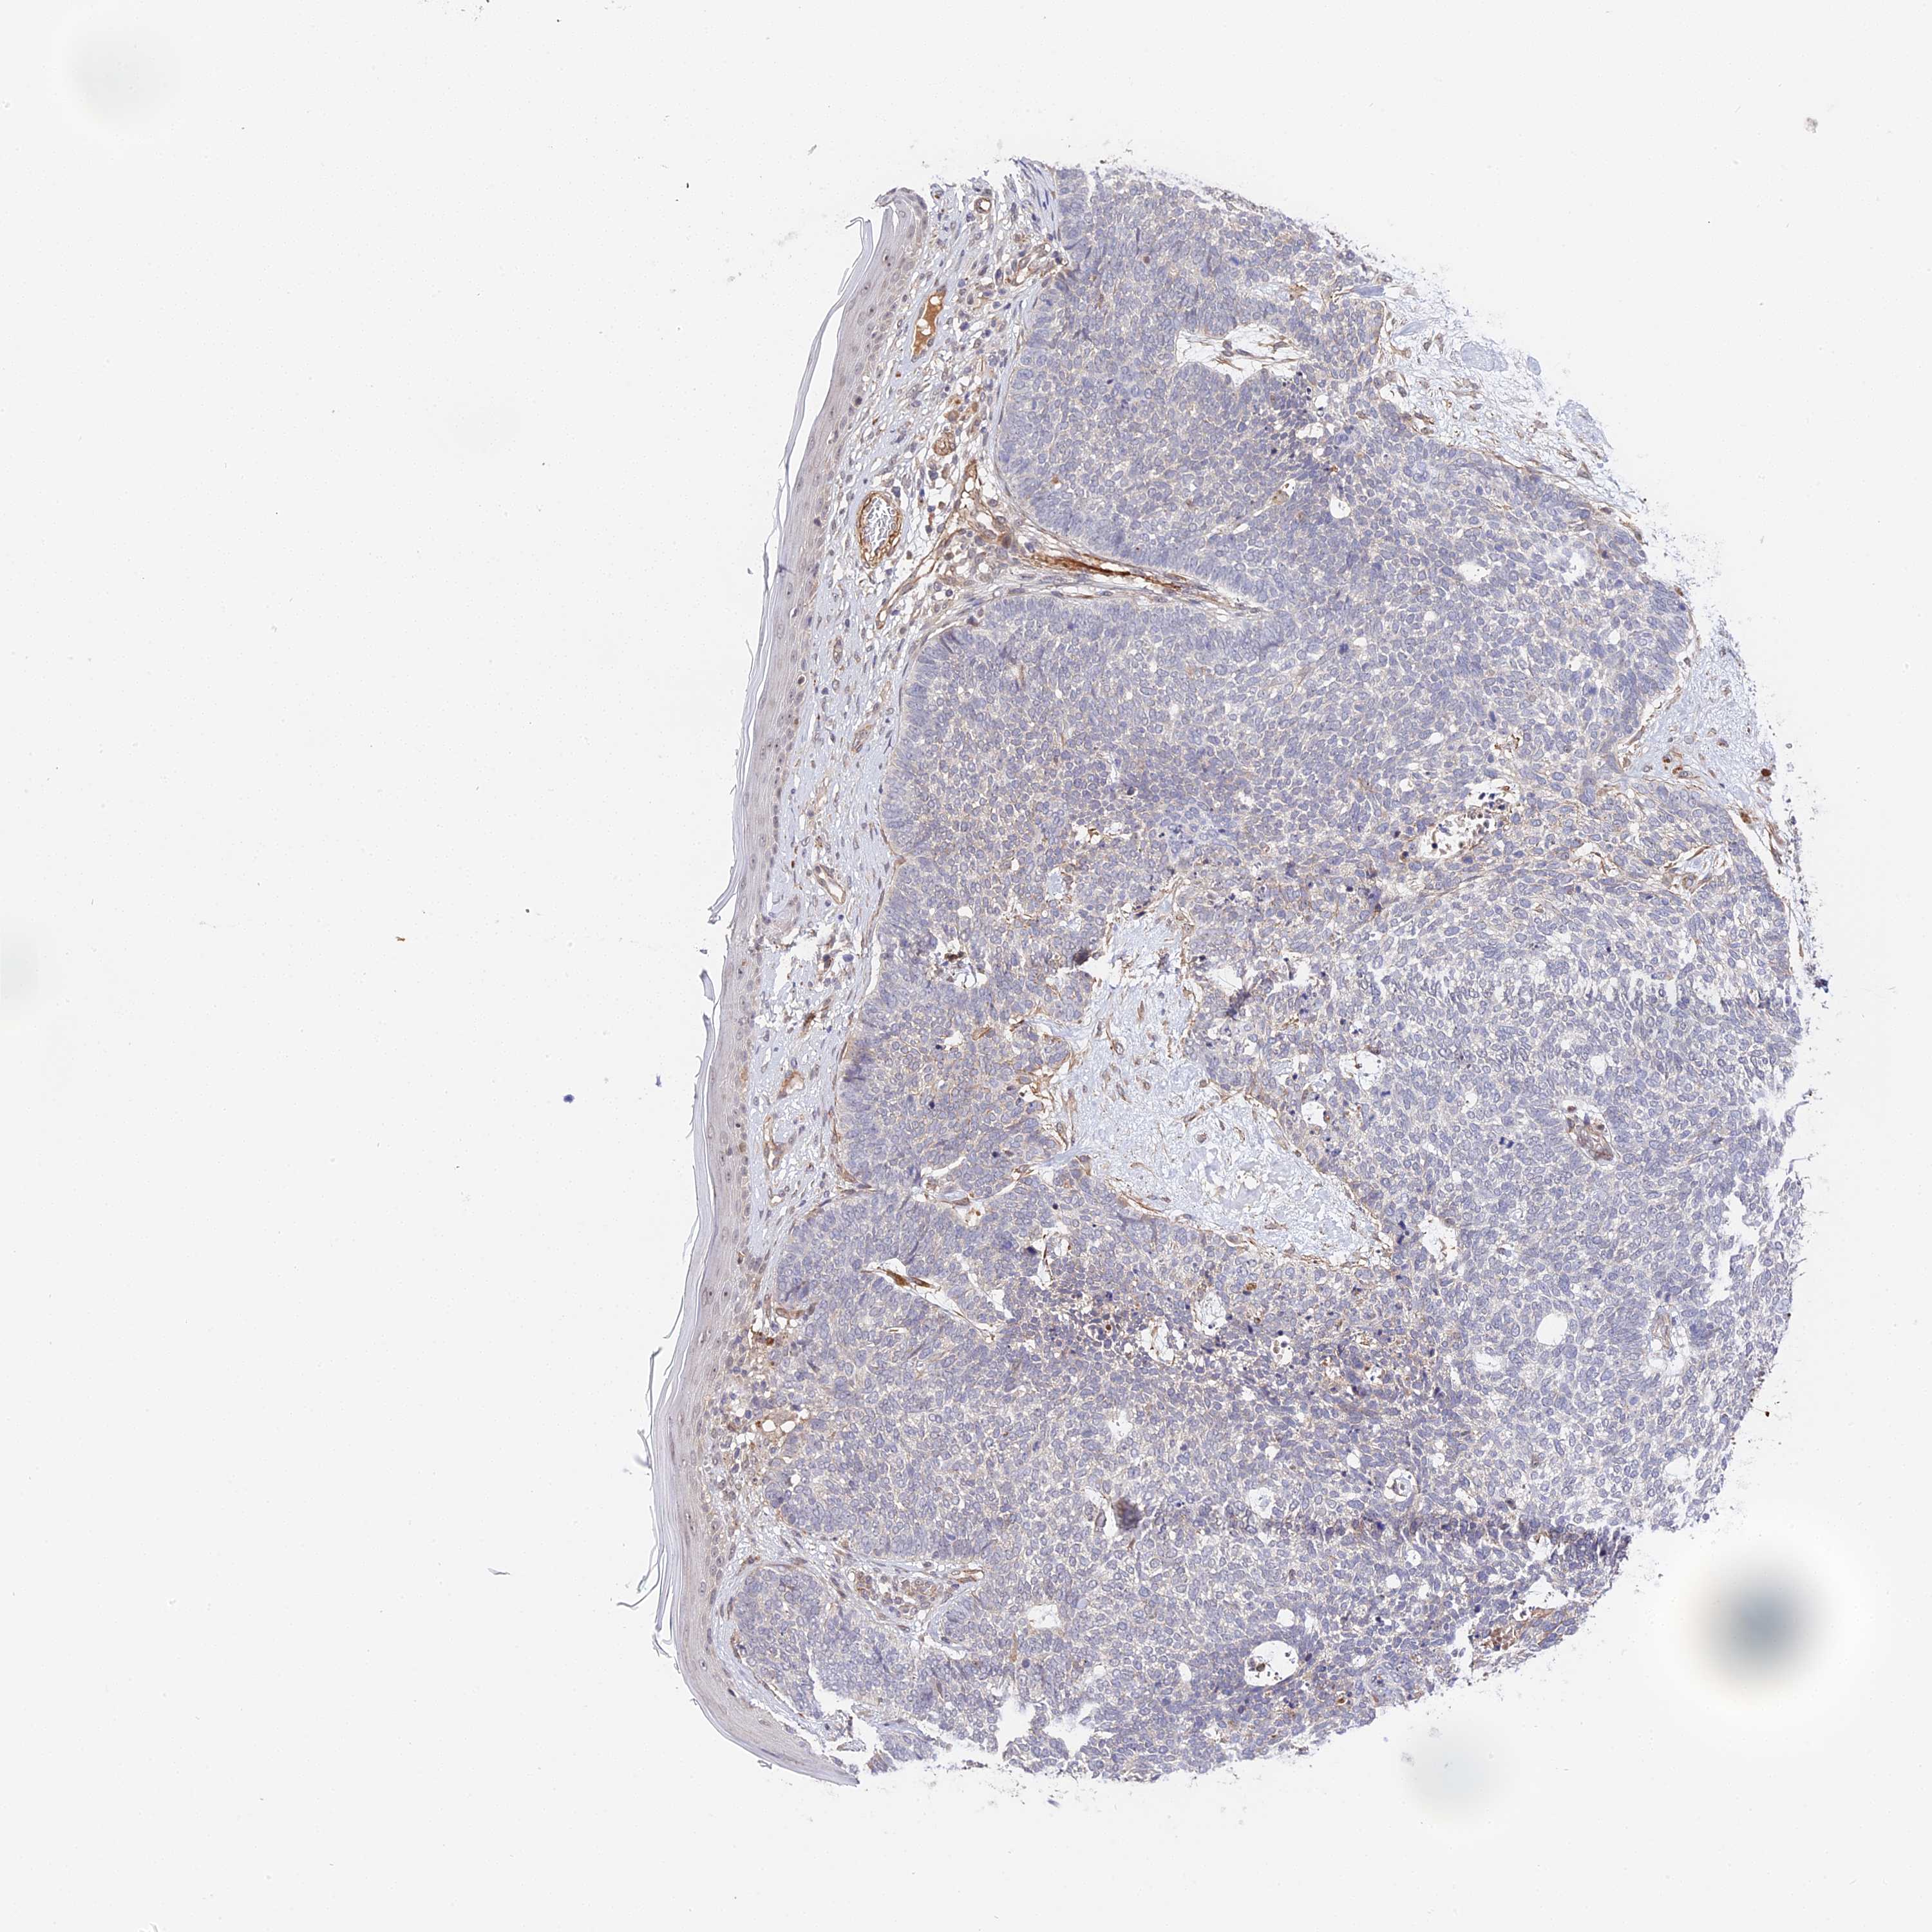

SKIN CANCER - Protein expressioni

A mouse-over function shows sample information and annotation data. Click on an image to view it in a full screen mode. Samples can be filtered based on level of antibody staining by selecting one or several of the following categories: high, medium, low and not detected. The assay and annotation is described here.

Antibody stainingi

Antibody staining in the annotated cell types in the current human tissue is reported as not detected, low, medium, or high, based on conventional immunohistochemistry profiling in selected tissues. This score is based on the combination of the staining intensity and fraction of stained cells.

Each image is clickable and will lead to virtual microscopy that enables deeper exploration of all samples and also displays staining intensity scores, fraction scores and subcellular localization as well as patient and tissue information for each sample.

Antibody HPA041045

Antibody HPA041968

Staining

High

Medium

Low

Not detected

Squamous cell carcinoma, NOS

Basal cell carcinoma